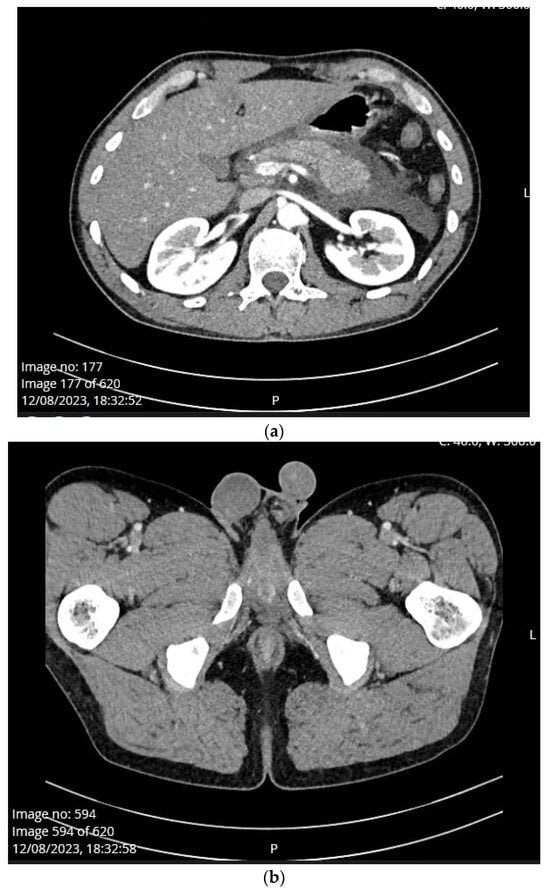

Case Presentation